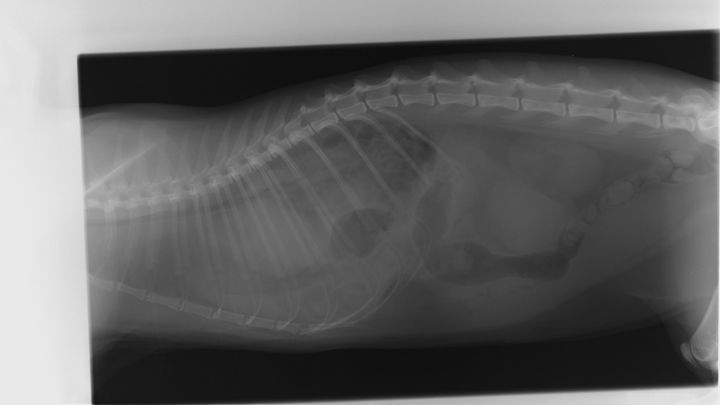

I’m reaching out because my cat, Phoebus, desperately needs life-saving surgery, and I can’t afford it on my own. Just two days ago, I took him to the vet after struggling for a long time to get him the care he needs. He has always had breathing issues, and I initially thought it was asthma. However, after an X-ray, the vet diagnosed him with a severe diaphragmatic hernia, a condition where a hole between his abdomen and chest has allowed his intestines to push into his chest cavity. This is crushing his lungs, making it incredibly difficult for him to breathe.